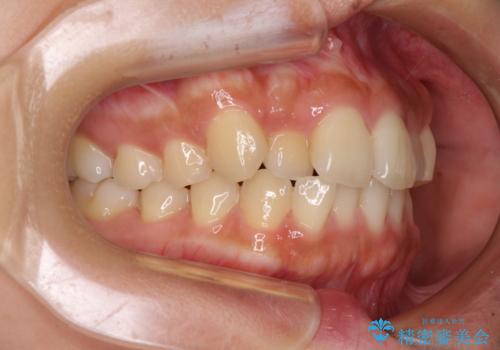

【モニター】歯列が狭くデコボコが気になる 急速拡大装置を用いたインビザライン矯正

- 奥歯の咬み合わせと治療を放置したまま奥歯を気にして来院された患者様です。

上顎骨の幅が下顎骨よりも小さいので、拡大装置により骨幅を広げて上下関係を改善し、その後インビザラインにて歯並びを整えることとしました。

上下の骨幅を改善したことで、スムーズに歯列矯正を行うことができました。

土台のまま放置されていた歯は土台の状態で咬み合っていましたが、急速拡大を行った際に咬み合わせが著しく挙上されたため、その際に土台を大きくすることで咬み合う歯との距離を確保しました。